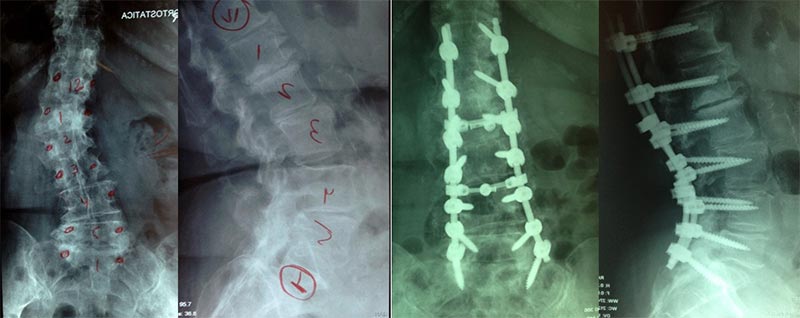

Artrodese longa da coluna e osteotomias:

Para aqueles pacientes os quais a deformidade é o principal fator causador da dor e disfunção (pior pontuação na classificação de Schwab) a correção total da deformidade no plano coronal e principalmente sagital deve ser objetivo da cirurgia além da descompressão de estruturas neurológicas. Para isso além da fixação pedicular e liberação das estruturas musculares e ligamentares geralmente se faze necessários técnicas de osteotomias para correção de todos os parâmetros.

As principais técnicas de osteotomias são à Smith Petersen ou Ponte (SPO), Subtração Pedicular (PSO) e a Vertebrectomia.

A osteotomia de subtração pedicular é uma cunha de fechamento posterior mais agressiva, capaz de corrigir de 30° a 40° por nível, faz o encurtamento das colunas anterior, média e posterior, equivale a três osteotomias Smith-Peterson, geralmente realizada com segurança nos níveis L2-L3, em pacientes com grave desequilíbrio no plano sagital. Apesar de muito efetiva é tecnicamente demandante, com riscos neurológicos e sangramento significantes.

Correção Cirúrgica de escoliose do Idoso